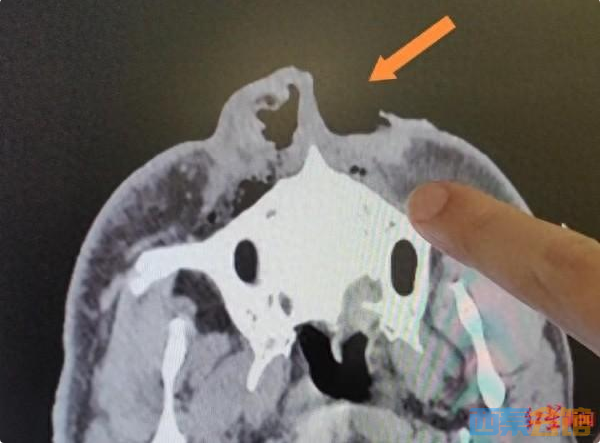

CT影像,鼻子被黑熊咬掉一半

6月15日晚11时许,救护车将何云光送达四川省人民医院急诊科,整形外科医生崔玮收到急诊科的通知,紧急前往会诊。“他的伤势比较严重,整个脸都是血肉模糊的,身上到处都是抓伤、咬伤。”崔玮说:“不过,不幸中的万幸,他的生命体征平稳,CT检查发现没有伤及颅脑和内脏。”

何云光全身的裂伤,共约10处,其中最严重的,是黑熊的撕咬在他脸上留下的一道约15厘米长的伤口,让他眼皮、眼睑受损,泪小管断裂,失去一半鼻子。由于各处伤口污物较多,因此首先进行了精心的清创和连续两天的引流,确保他伤口内部的污物能够排出。